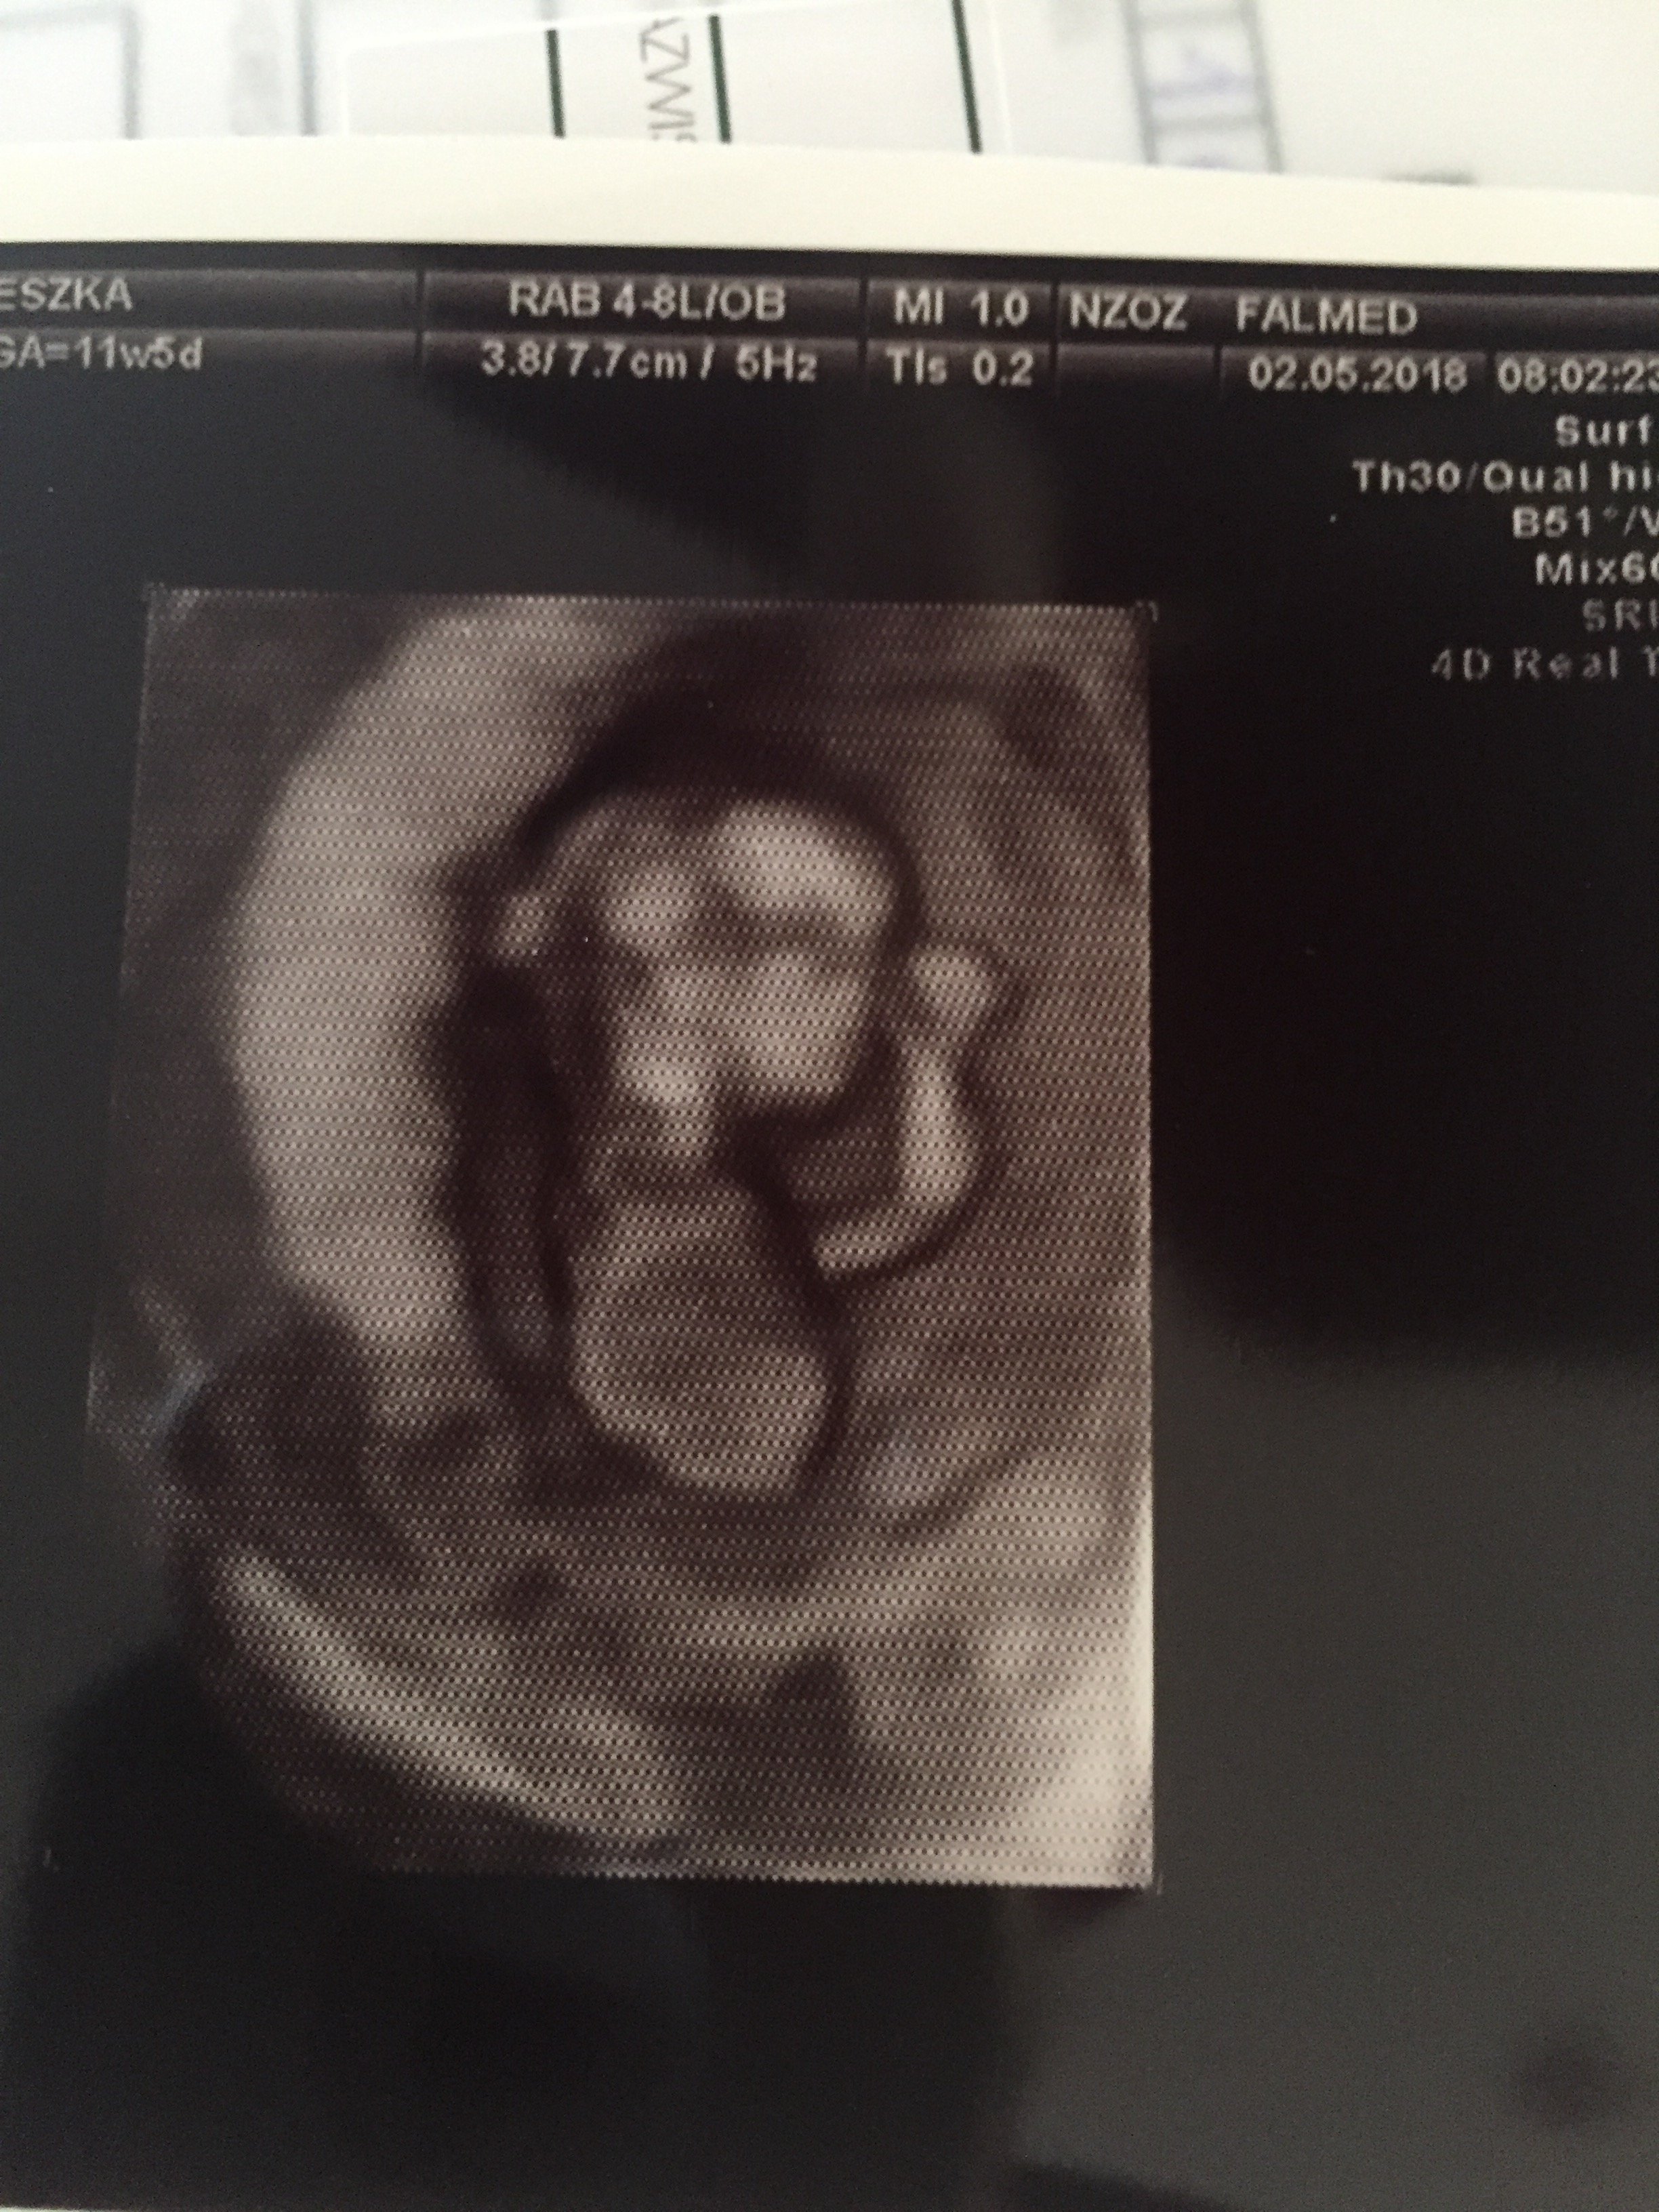

Jestem po badaniach prenatalnych z usg wszystko Ok teraz czekamy na wyniki krwi.

U mnie z usg dzidzia starsza o tydzień.

Widzę że macie zdjęcia Kochanych bobasków może i mi się uda wstawić bo jak na razie badam temat co i jak :D

Załączniki

• E2580A3A-BBA4-48E4-821B-8C6A811CA3D1.jpeg

E2580A3A-BBA4-48E4-821B-8C6A811CA3D1.jpeg

1,1 MB · Wyświetleń: 131